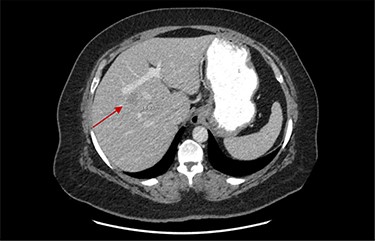

On assessment, the patient denied any symptoms related to her neuroendocrine tumor, including flushing, increased sweating, increased heart rate, wheezing, shortness of breath, diarrhea, weight loss or appetite changes. The only significant family history was a paternal and maternal grandfather with colon cancer. Imaging results were significant for computed tomography (CT) of chest demonstrating very small, but multiple, pulmonary nodules. A CT abdomen and pelvis demonstrated the known neuroendocrine tumor near the ileocecal valve (Fig. 1) as well as two poorly visualized liver lesions (Figs 2–4). The magnetic resonance imaging (MRI) demonstrated two separate one-centimeter lesions in segment 5 and 7 of the liver (Figs 5 and 6). The portal vein lacked normal left and right bifurcation; there was a circumferential right portal vein, which coursed anteriorly and superiorly and ultimately to the left lobe of the liver.